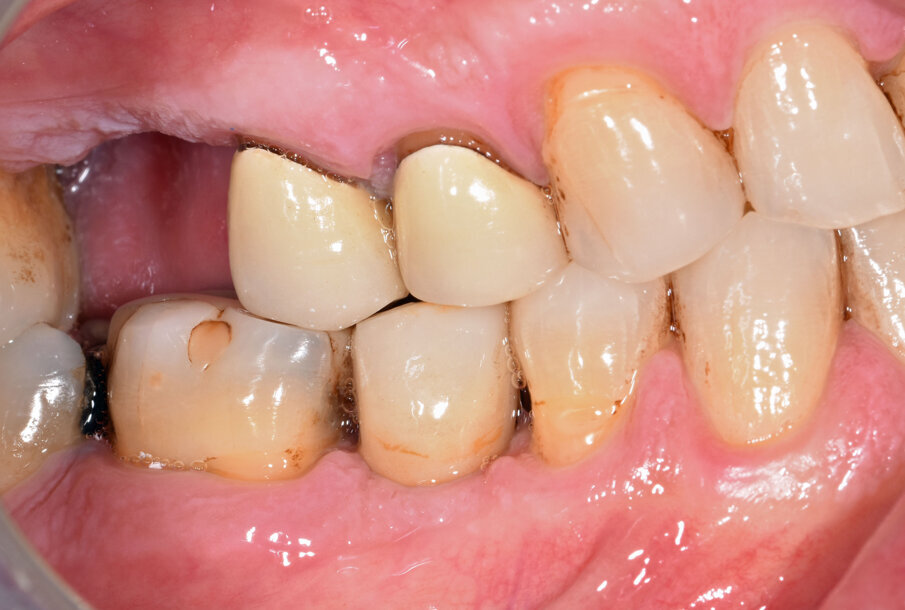

G. I. paziente di anni 50, si presenta alla nostra osservazione con una frattura longitudinale della radice dell’elemento 4.5 dovuta a infiltrazione cariosa della vecchia corona protesica. Questa situazione ha provocato nell’osso alveolare del paziente una grossa lesione che è andata ad interessare anche la corticale vestibolare. Per poter sostituire la radice con un impianto sarebbe necessario un intervento di chirurgia ossea rigenerativa ma un’alternativa meno invasiva è la rigenerazione del tessuto osseo ottenuta tramite l’estrusione forzata dell’elemento che rigenera osso durante la sua lenta migrazione grazie al legamento parodontale. In accordo con il paziente, dopo opportuna spiegazione dei benefici e dei tempi dell’approccio con estrusione ortodontica, si decide di procedere con questo iter evitando così l’intervento di rigenerativa.

Dopo 3 mesi dall’inserimento implantare è stato possibile prendere un’impronta e di precisione e realizzare una corona singola avvitata.